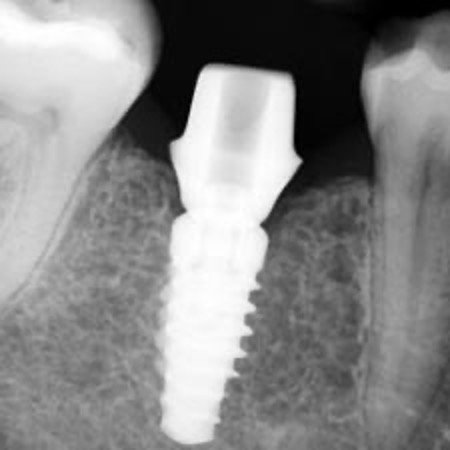

Dental implants are the gold standard for replacing teeth that can't be saved.

Strong, natural-looking, and long-lasting, implants restore both function and appearance—giving you the confidence to eat, speak, and smile with ease

Implant crowns can stand alone and can also be used to support bridges and dentures